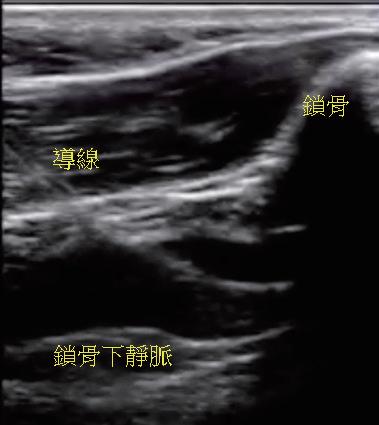

臺大兒童醫院兒童心臟科在吳美環教授與邱舜南 教授的率領下,於 2016 年底開始進行無輻射心律不 整燒灼,並於 2018 年開始發展 EnSite Precision 心臟 定位系統輔助進行無輻射心臟植入性電子儀器放置。 病患在以 propofol 鎮靜和 lidocaine 局部麻醉後,藉由 無菌的超音波即時導引技術,穿刺左鎖骨下靜脈或左 腋靜脈並留置導線(圖一),接著先於鎖骨下區域手

術製造皮下口袋(subcutaneous pocket)後,再以導線 經 Seldinger technique 建立靜脈的通道。接著,藉由 EnSite Precision 心臟定位系統,使用可控式 10 極導管 ( InquiryTM, steerable diagnostic catheter, SJM ), 自左鎖骨下靜脈、頭肱靜脈 , 上、下腔靜脈、右心房 以及右心室等立體結構,進行心血管系統之 3D 繪製 (圖二)。繪製時,會特別著重右心耳、右心尖與右 心室出口的結構與位置,以利後續置放進行。接著, 將心臟植入性電子儀器的導線連結於 EnSite 系統並成 像,在 3D 定位系統導引下,由先前繪製的構造中, 將導線尖端置於目標處(圖三),並進行相關參數測 試。選定適當位置進行導線固定時,由於目前系統無 法將主動固定的螺旋( screw)成像,因此無法確認螺 旋是否確實伸展。我們團隊於此步驟會藉由螢光檢查 檢視螺旋伸展的狀況、評估放置位置是否與預期相符 以及導線鬆弛程度( lead slack)是否適當。調整後, 完成心臟植入性電子儀器放置時,亦會再藉由螢光檢 查確認位置(圖四)。目前臺大單一中心經驗,藉由 3D 定位系統於 13 個病人中放置過 14 個儀器(3 個單 腔節律器、6 個雙腔節律器、4 個植入式心內去顫器及 1 例心臟再同步治療裝置),平均輻射暴露時間約為 0.6 分鐘,相較於傳統方式(平均輻射暴露時間為 10.3 分 鐘)明顯少許多。目前無觀察到相關術後併發症,且 各儀器的追蹤參數與傳統置入的儀器無差別。 相較於置放節律器與植入式心內去顫器,心臟再 同步治療裝置的更為複雜,因為需將導線置於冠狀 靜脈竇(coronary sinus, CS),可能需要藉由顯影劑 讓 CS 顯像,且所需的輻射暴露時間常為前兩者的數 倍 (14),病人與執行醫師的輻射暴露也最強,過去甚至 有研究建議一位醫師單月放置心臟再同步治療裝置數 目勿超過四個,以控制在較安全的輻射曝露量 (15)。